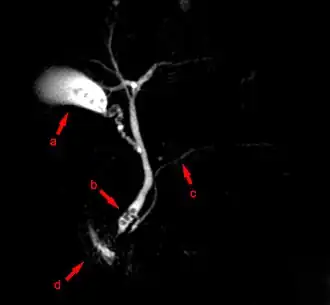

Лучевая диагностика

При исследовании печени, поджелудочной железы и жёлчных протоков ведущую роль занимают ультразвуковые исследования (УЗИ), компьютерная томография (КТ) и магнитно-резонансная томография (МРТ). При диагностике состояния пищевода распространено рентгеновское исследование с барием, при котором прохождение глотков бариевой взвеси регистрируется флюороскопически в реальном масштабе времени. Рентгенография пищевода применяется для выявления грыж пищеводного отверстия диафрагмы, опухолей, дивертикулов, стриктур, варикозного расширения вен, инородных тел. Рентгенография или рентгеноскопия с двойным контрастированием или без него применяется при исследовании желудка и двенадцатиперстной кишки с целью выявления язв, опухолей, стриктур, обтураций, контроля результатов оперативных вмешательств. Для диагностики опухолей кишечника, воспалительных заболеваний, причин непроходимости кишки, стриктур, обструкции применяется контрастная рентгенография, компьютерная или магнито-резонансная томография[28].

- Лучевая диагностика болезней ЖКТ

- Магнито-резонансный томограф

МРТ-изображение содержащих камни жёлчного пузыря и протоков

МРТ-изображение содержащих камни жёлчного пузыря и протоков

См. также